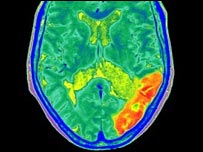

Taxa de mortalidade por derrame é maior em fins-de-semana

Cérebro com derrame

Pesquisadores canadenses analisaram taxa de mortalidade por derrame

Pacientes internados com derrames cerebrais nos finais de semana têm mais chances de morrer, de acordo com um estudo da Universidade de Toronto, no Canadá.